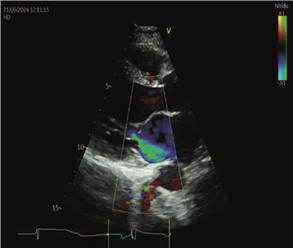

FEVI 40-41%, AI moderadamente dilatada. Insuficiencia mitral leve. Insuficiencia tricuspídea leve con presión sistólica de la arteria pulmonar de 24 mmHg. Sin otros cambios con respecto al ecocardiograma previo al embarazo (figuras 1 y 2).

Figura 2. Ecocardiograma Doppler Transtorácico que muestra apicalización del cierre de la válvula mitral con tenting asimétrico que genera jet de regurgitación excéntrico de grado moderado.